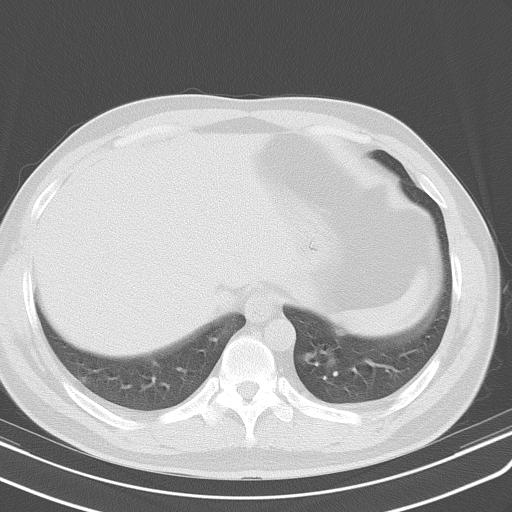

患者男性 35 主因发热咳嗽四天,血象不高,心肺听诊未见异常,无其它病史及传染病接触史。

一周后复查胸片基本正常

经一周抗炎抗病毒治疗复查胸片示病变大部吸收,基本恢复正常,未做气管镜检查,考虑为炎性变或霉菌感染。